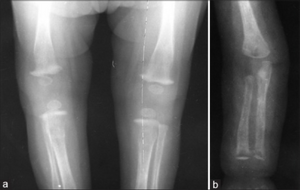

The proximal tibial metaphyses reveals loss of density on the medial aspect along with periosteal reaction, suggestive of osteochondritis (Wimberger's sign). Distal metaphyses of the humerus also showed periosteal reaction

The Wimberger sign refers to localized bilateral metaphyseal destruction of the medial proximal tibia.[1] It is a pathognomonic sign for congenital syphilis.[2]